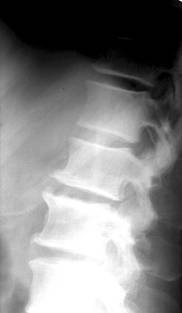

Modificarile radiologice ale spondilodiscitei tuberculoase sunt:

foarte mici focare osteolitice in apropierea discului, adesea invizibile radiografic;

diminuarea inaltimii spatiului discal ce antreneaza modificari de ax ale coloanei vertebrale (cifoza sau scoliaza);

stergerea suprafetelor discale si structura neomogena a corpurilor vertebrale adiacente discului, cu zone de osteoliza imprecis delimitate; localizarea leziunilor distructive fata-n fata pe cele doua platouri vertebrale implicate realizeaza asa zisa imagine “in oglinda”;

deformarea si reducerea, uneori extrema, a inaltimii corpilor vertebrali cu modificari de ax ale coloanei (cifoza pottica), dislocari, luxatii;

abcesul rece (pottic) apare ca o opacitate uni sau bilaterala ce proemina lateral, omogena, bine delimitata, depasind apofizele transverse. Abcesele din regiunea toracala medie nu migreaza la distanta si stagneaza in spatiul costovertebral sau intercostal, putand eroda coastele. Abcesele toracolombare coboara uneori pe teaca psoasilor in regiunea lombara, astfel ca vor modifica (bomba) umbra psoasului. Abcesele din regiunea cervicala deplaseaza anterior traheea si esofagul;

modificari reconstructive sub forma liniilor de demarcatie, zone de ingrosare a structurii osoase ce delimiteaza leziunea si fac sa reapara conturul vertebral care se recalcifica;

tardiv apar punti osoase intervertebrale ce demonstreaza fuziunea dintre vertebre;

evolutia fara tratament duce la distrugeri importante ale corpurilor vertebrale, aparitia sechestrelor si mari modificari de statica.